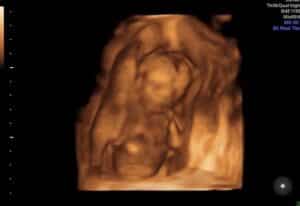

Baby Girl On The Way

I am 16 weeks and confirmed baby girl 💗 !

So in love and we can not thank Dr. Monteith enough.